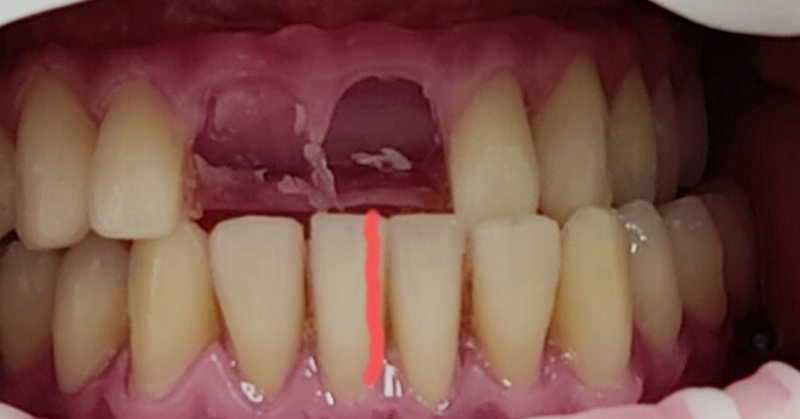

Fast zahnlos über Jahre: Drei Kronen mit Lokatorenspitzen.

Praktische Zahnlosigkeit über Jahre - Erschwerte Therapie durch Makroglossie

Ein Fallbericht von Daniel Liss – Zahnarzt im AllDent Zahnzentrum Leipzig

Der Fall zeigt, dass auch unter widrigen Umständen (lange Zahnlosigkeit, Makroglossie) Full-Arch-Sofortversorgungen auf vier Implantaten möglich sind. Trotz oder möglicherweise gerade wegen der langen Zahnlosigkeit war der Patient bereits mit den provisorischen Brücken sehr gut zurechtgekommen. Durch die Perfektionierung des Bisses konnten Freude und Zufriedenheit über die neuen Zähne noch gesteigert werden. Auch das Behandlungsteam durfte sich schließlich über die erfolgreiche Bissrehabilitation und das Einhalten der guten medizinischen Standards freuen.